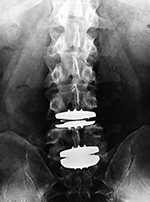

Metal-on-polyethylene total disk replacement at L4-5 and L5-S1 |

| Lumbar spine fusion and metal-on-polyethylene disk replacement at L4-5 and L5-S1 |

| 31 year-old man with chronic low back pain. In addition to the total disk replacements at L4-5 and L5-S1 there is also a laminectomy from L4 to S1 with posterolateral bony fusion masses and pedicle screws with connecting rods on each side. |